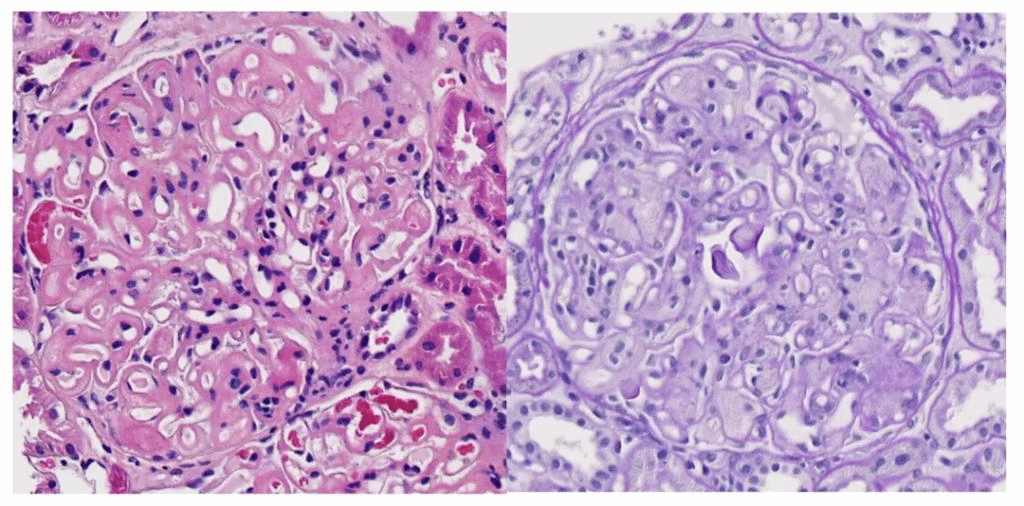

2023年12月8日,新医大一附院肾脏疾病中心收治了一例特殊的患者,该患者临床表现为肾脏受累,符合常见的慢性肾炎综合征,但肾穿刺活检病理诊断不寻常,经电镜检查发现肾小球系膜区和基底膜有大量带横纹的束状胶原纤维,直径在40~70 nm。为了明确诊断,进一步通过全外显子检查除外法布雷病,加做免疫组织化学染色表现为Ⅲ型胶原纤维阳性。

左图:HE 右图PAS